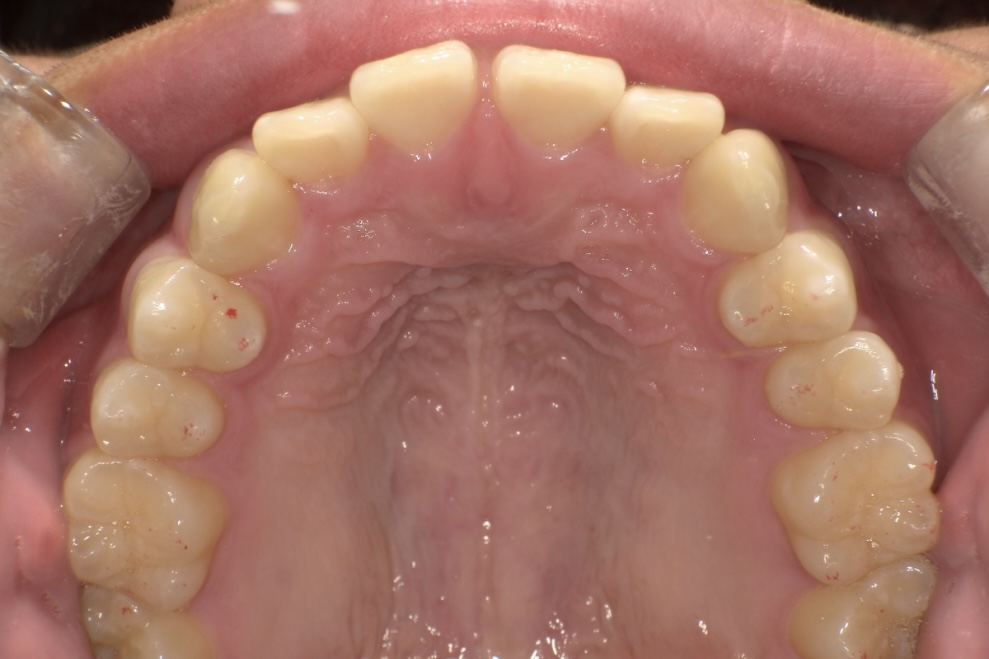

治療期間は1年半で、すき間が改善され、口元の印象が大きく変化しています。

BEFORE

AFTER